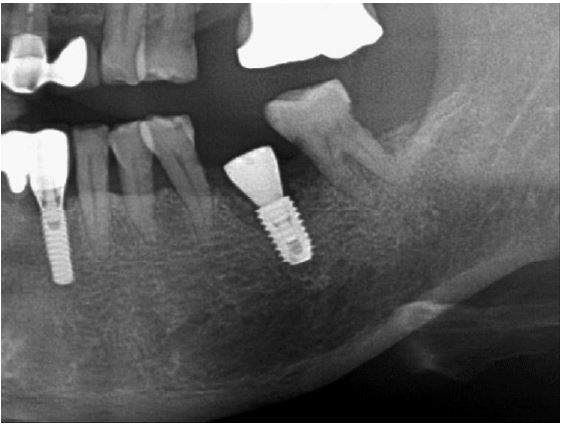

Radiographic examination confirmed root caries and apical lesions in the maxillary left second molar (Fig. 12). It was predicted that the initial stability could be achieved, and extraction and iARP were planned. The patient was instructed to rinse with 0.12% chlorhexidine digluconate solution for 2 minutes for oral disinfection. The left second molar was extracted using luxators and extraction forceps under local anesthesia with 2% lidocaine containing 1:80,000 epinephrine (Fig. 13A, 13B). After debridement of granulation tissues in the apical area and irrigation with a sterile normal saline solution, immediate implant placement (TS III 5.0 × 8.5 mm; OSSTEM) was performed (Fig. 13C). The ISQ value at first surgery was 60. The gap between the implant surface and the extraction socket wall was filled with DBBM and covered with NBCM in a double-layer fashion (Fig. 13D, 13E). The hidden X suture and horizontal mattress suture were placed over NBCM without primary wound closure (Fig. 13F, 13G). Fourteen days after surgery, the patient returned for suture removal and postoperative examination. Healing of the depressed soft tissue above the extraction socket is observed. After four weeks, soft tissue depression continued, but epithelial healing was complete (Fig. 13H, 13I).

Fig. 13.

Case 3: Clinical photographs of the immediate implant placement with alveolar ridge preservation. (A) Initial clinical photograph of the left maxillary second molar, (B) The tooth was extracted without any gingival damage, (C) Immediate implant placement in the left maxillary second molar, (D) Deproteinized bovine bone mineral is placed in the extraction socket and covered with a native bilayer collagen membrane, (E) Extraction socket and covering with native bilayer collagen membranes, (F) Hidden X and horizontal mattress sutures are placed, (G) Panoramic radiograph obtained after implant placement, (H) Yellowish, depressed gingival healing observed at the stitch removal (2 weeks), (I) Depressed gingival healing was observed without inflammation at recall check (4 weeks).

Four months after the first surgery for the implant, reopening for the second surgery, the site demonstrated that the fixture was surrounded by new bone, and the ISQ value was 68 (Fig. 14A, 14B). Subsequently, a 6.0 mm diameter, 7 mm length healing abutment was placed (Fig. 15).